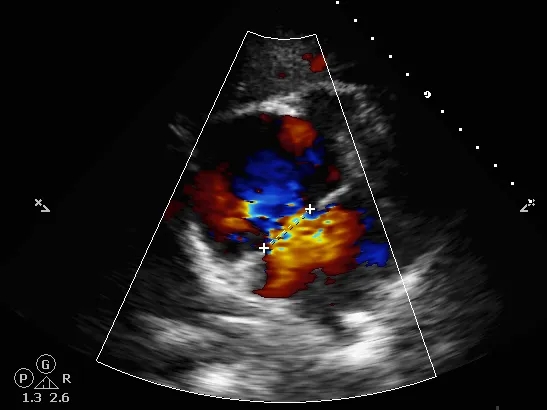

术中复测

超声可见房间隔连续中断,彩色多普勒可见过隔血流

测量房间隔缺损直径最大为23.9mm,房间隔总长53.8mm